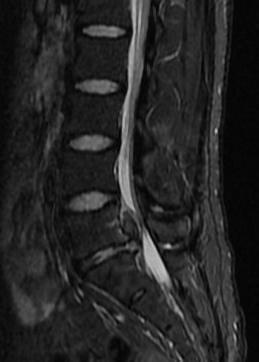

29歲男性,L5/S1椎間盤脫出,經(jīng)椎板間入路椎間孔鏡下行椎間盤摘除,術(shù)中取出大塊椎間盤組織,術(shù)后癥狀明顯緩解。